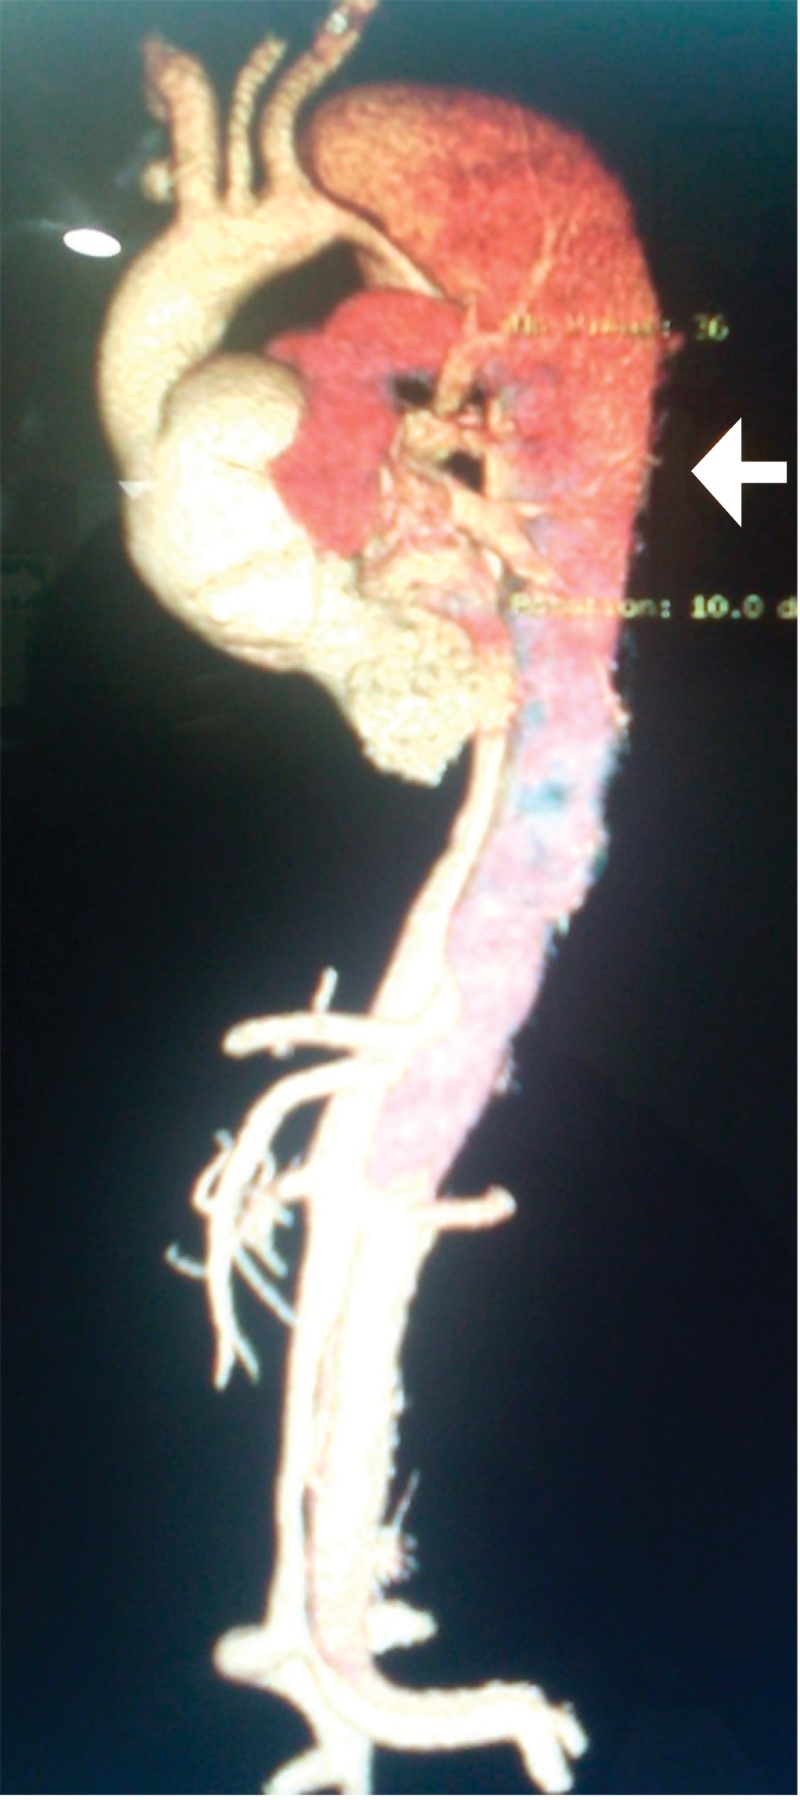

Acute aortic syndromes. A diagnosis to consider in the Emergency Department

Figure 1

Figure 2

Figure 3